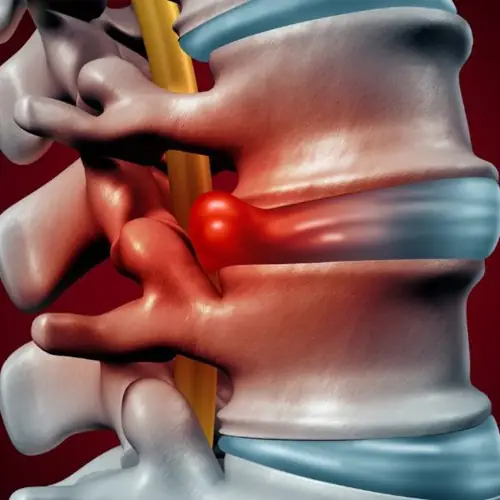

In fact, each vertebra is connected to the neighboring one by three joints: the main structure, called the vertebral disc, consists of cartilaginous tissue and plays the role of a shock absorber, and the other two, called facet joints, are filled with lubricant and work as hinges. This intricate design keeps the vertebral column stable and strong while allowing it to twist, or bend to the front, back, or side.

4. Spinal disc is damaged

Spinal discs are stronger and can withstand more severe stress than the mobile joints of the body, but they also tend to deteriorate due to wear and tear with aging. This increases the risk of disc bulge when the discs’ soft material protrudes into the spinal canal, irritating the nerves and causing pain, numbness, or weakness.

Improper massage technique, especially repetitive flexion and rotation of the trunk, and exerting too much force and pressure may exacerbate these symptoms. But, fortunately, such disc injuries are usually minor and heal on their own within a few days or weeks unless the disc had been previously badly damaged or heavily worn out.

Despite horrifying rumors of people having their backs broken during a Thai massage, there is no known case in Thailand where a spinal disc has been badly damaged while being massaged. Thai hospitals are required to report serious injuries to regulatory authorities, and such a case would have gone public.

Nevertheless, in the most unfortunate case, this can happen. Should this occur, the popping sound of disc rupture will be accompanied by sharp throbbing pain and inability to move. This trauma will require immediate medical attention, right up to surgery!